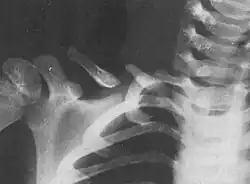

Beim Menschen tritt das Schlüsselbein paarig auf. Ein einzelnes Schlüsselbein des Menschen ist etwa 12–15 cm lang und S-förmig. Es besitzt zwei Enden und ein Mittelstück (Corpus claviculae). Das zur Körpermitte gerichtete (mediale) Ende wird als Extremitas sternalis (zum Brustbein hinzeigend) bezeichnet und besitzt eine runde Gelenkfläche, Facies articularis sternalis, die Teil des Gelenks zwischen Brust- und Schlüsselbein, Articulatio sternoclavicularis genannt, ist. Das seitliche Ende – als Extremitas acromialis (zur Schulterhöhe hinzeigend) bezeichnet – bildet ein Gelenk mit der Schulterhöhe (Acromion), das Schultereckgelenk (Articulatio acromioclavicularis), die Teil des Schulterblattes ist. Die entsprechende Gelenkfläche, die sattelförmig abgeflacht ist, wird Facies articularis acromialis genannt.

Beim Menschen kann es bei Stürzen auf die Schulter, direkt auf das Schlüsselbein oder selten auch auf den ausgestreckten Arm zu Brüchen des Schlüsselbeins (Klavikulafraktur) kommen. Mit etwa 15 % aller Knochenbrüche bricht die Clavicula am zweithäufigsten. Symptome sind unter anderem eine sicht- und tastbare Stufenbildung, eine scheinbare Verlängerung des Armes und Veränderungen der Kopfhaltung.